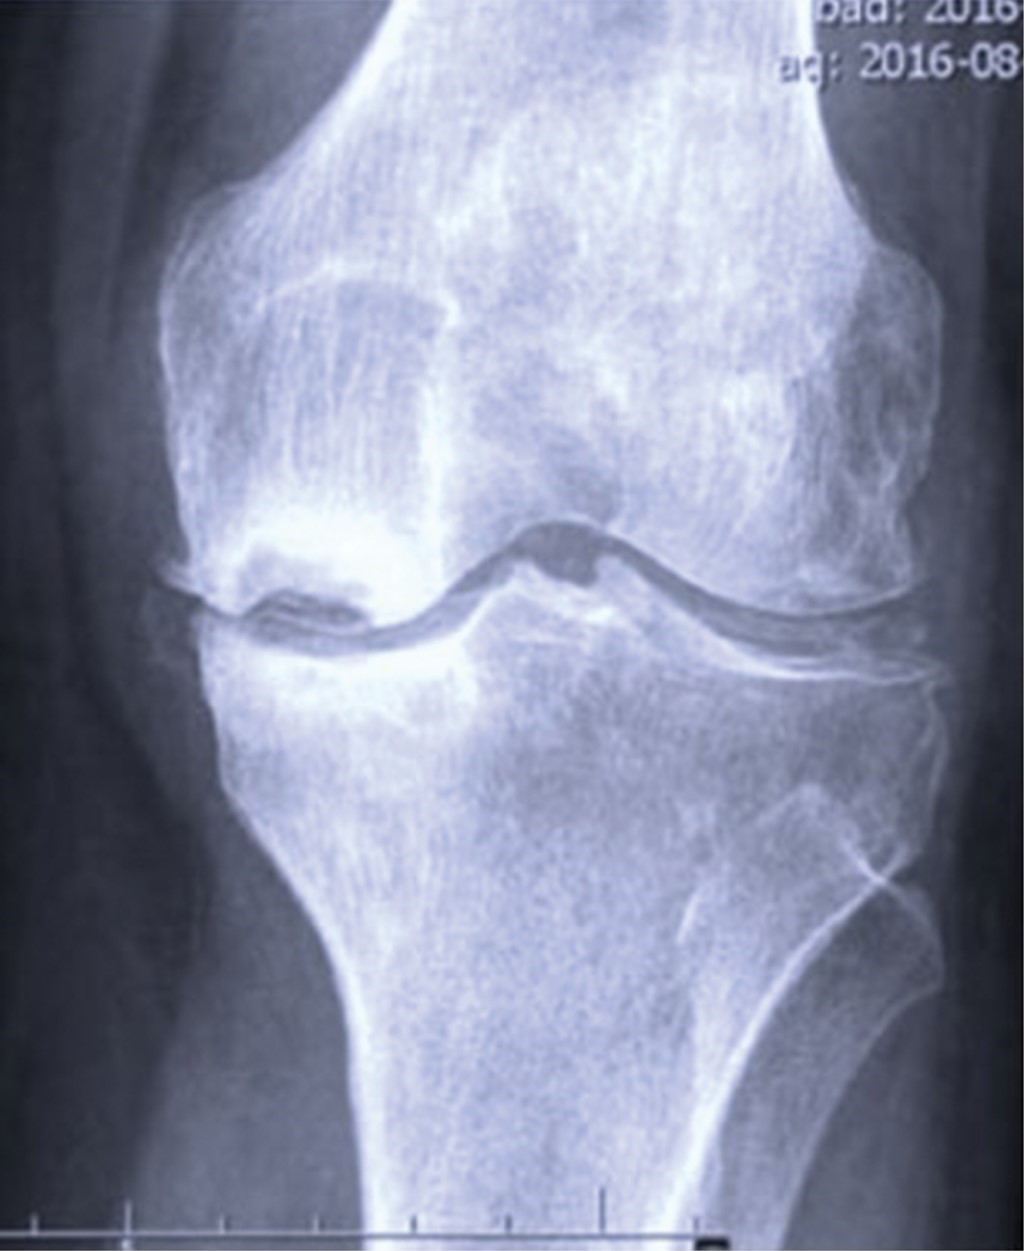

RADIOGRAFíAS SIMPLES

Durante la evaluación inicial, se recomienda realizar radiografías anteroposteriores, laterales y oblicuas. Sin embargo, en las primeras fases de la enfermedad, estas radiografías suelen mostrar resultados negativos, también se puede observar radiolucidez del hueso subcondral rodeada de esclerosis o aplanamiento de los cóndilos afectados. En fases más avanzadas, puede producirse colapso del hueso subcondral (Figura 1).22

Figura 1